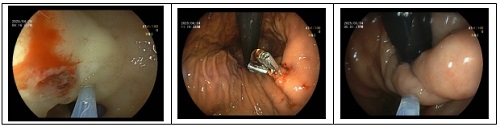

内镜下开展的手术

4.内镜下止血术